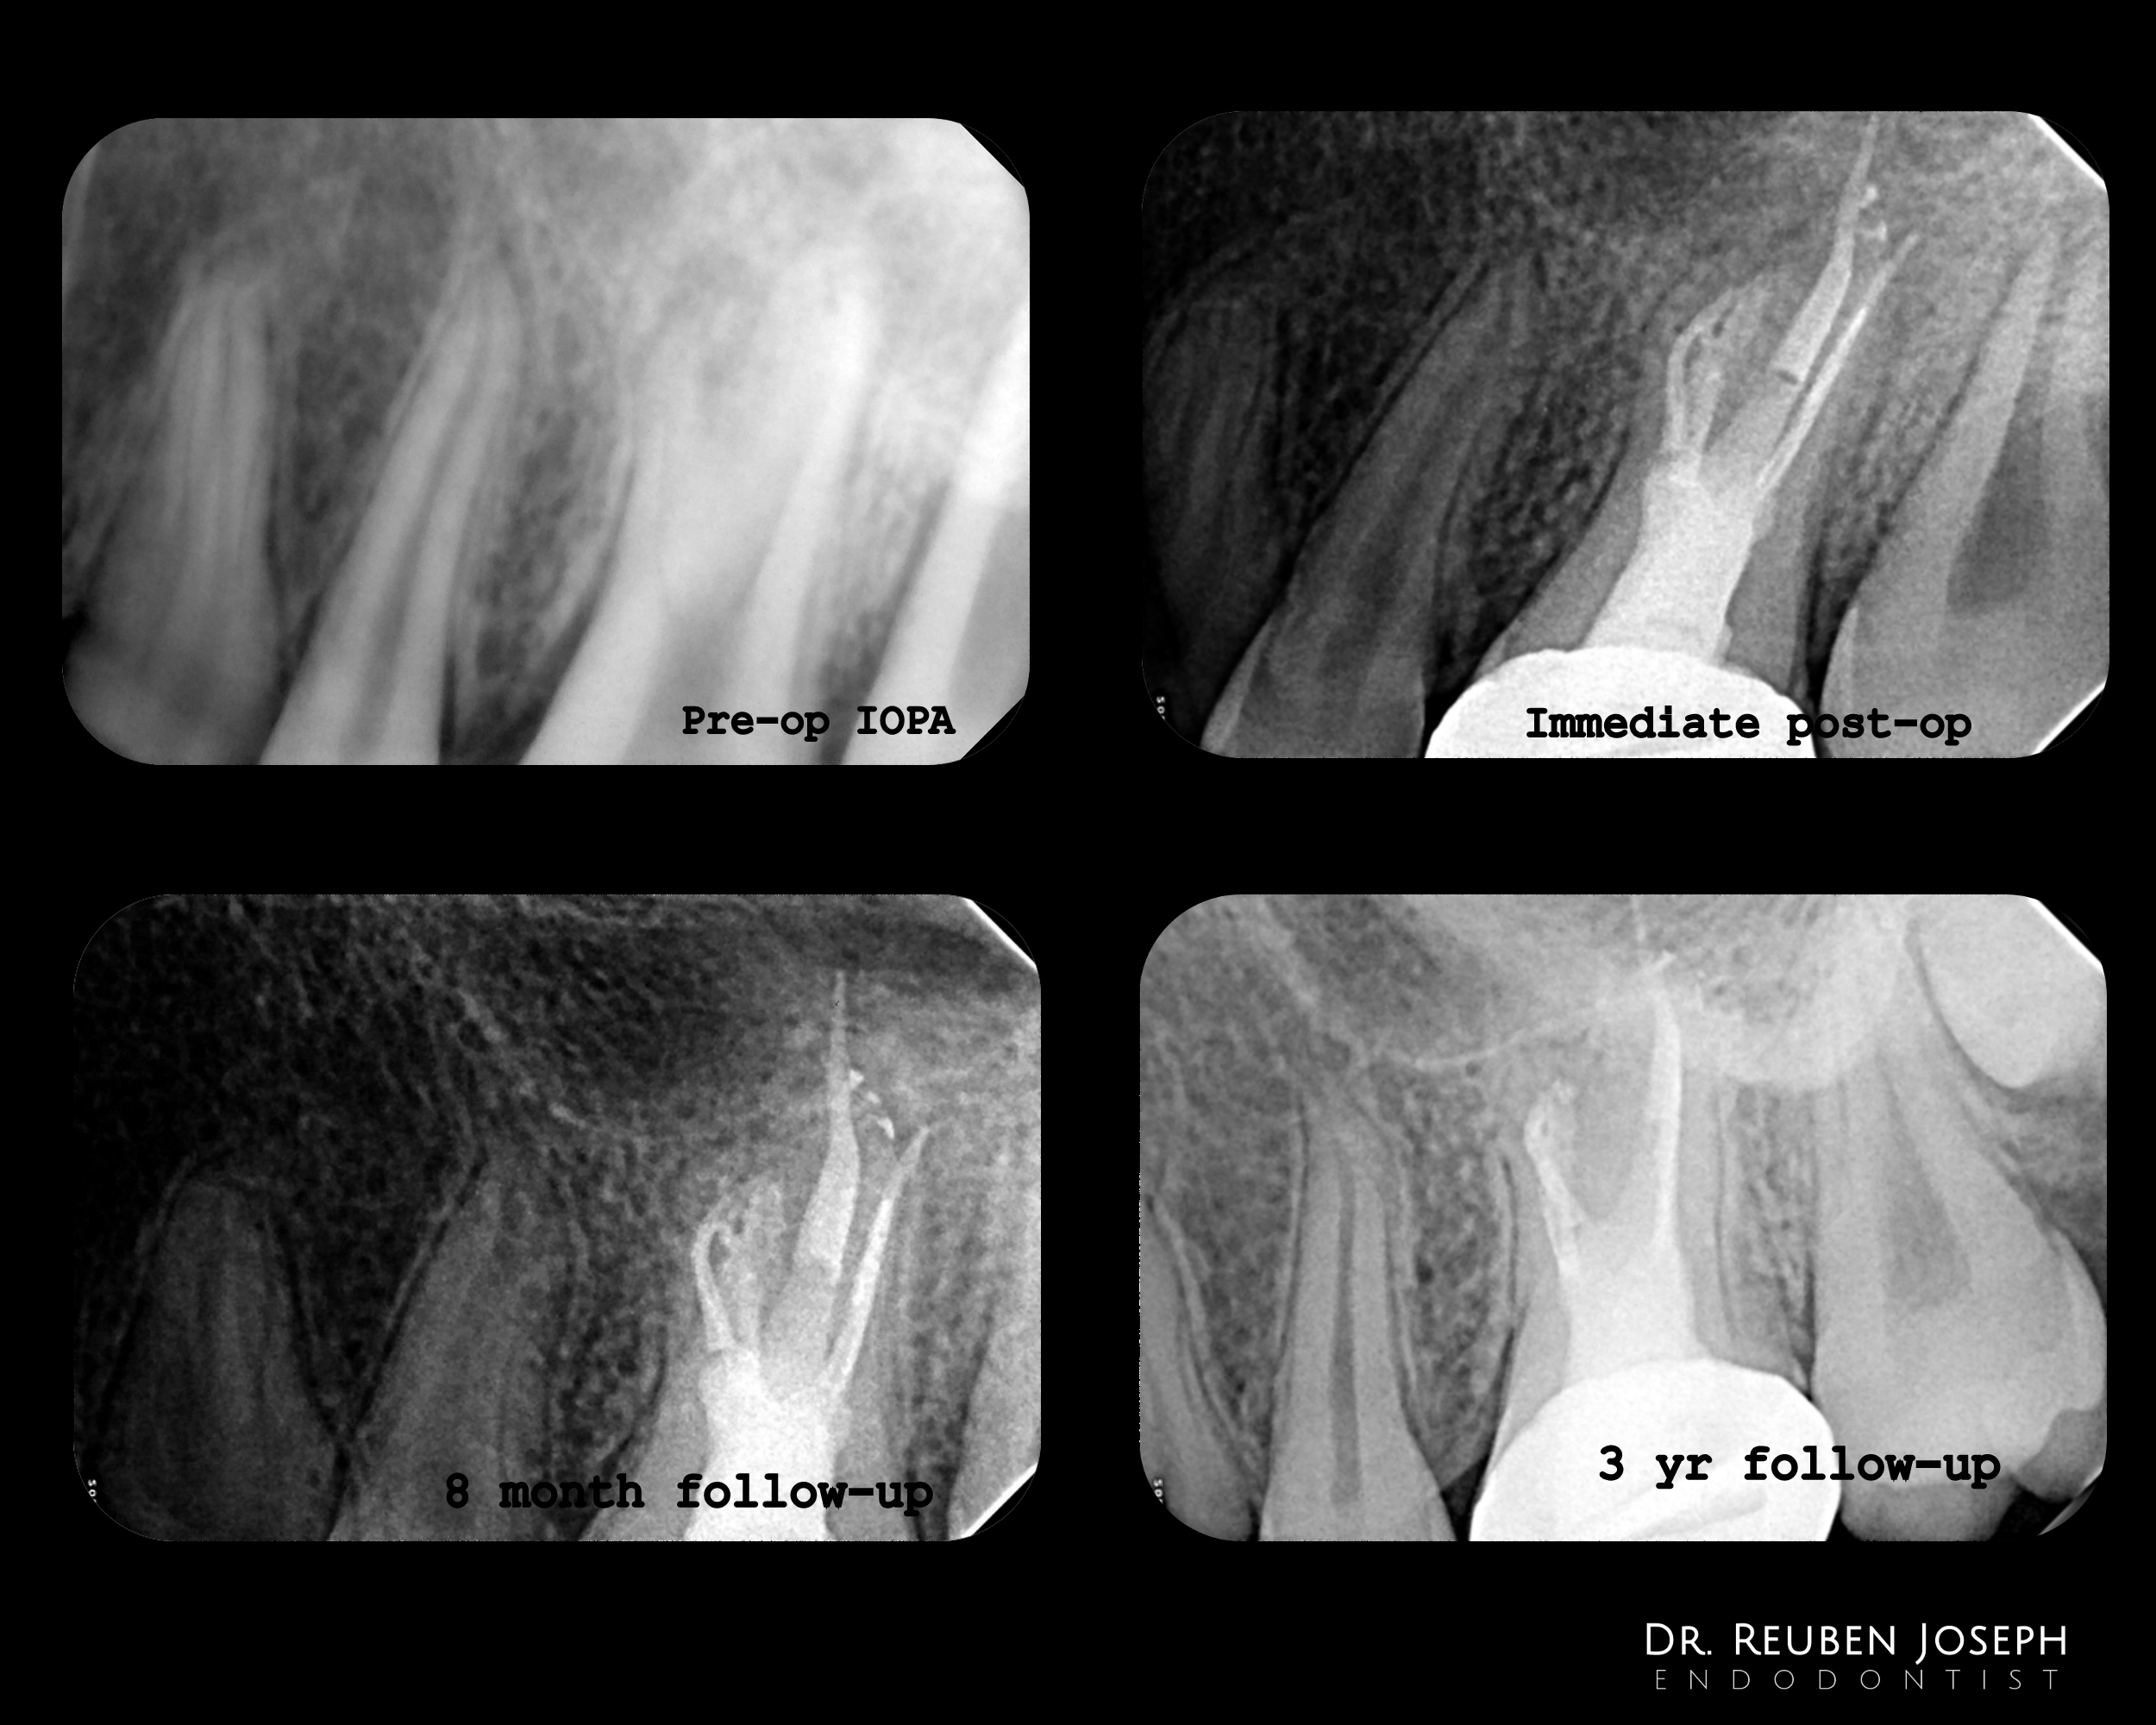

– Pt age 13yrs old then

– IOPA revealed a taurodontic anatomy and a PA lesion in relation to the palatal root.

– On access the floor was completely calcified and appeared bleached and ovoid. Managed to localize all canals which were in eccentric locations

– I noticed that I had pushed GP outside the palatal canal which showed multiple POE’s. Decision was made to leave it as it is and keep the tooth under observation and not attempt to remove the GP for fear of the apical extruded segment shearing off.

– 3yrs follow up showed a asymptomatic patient and a well healed lesion.